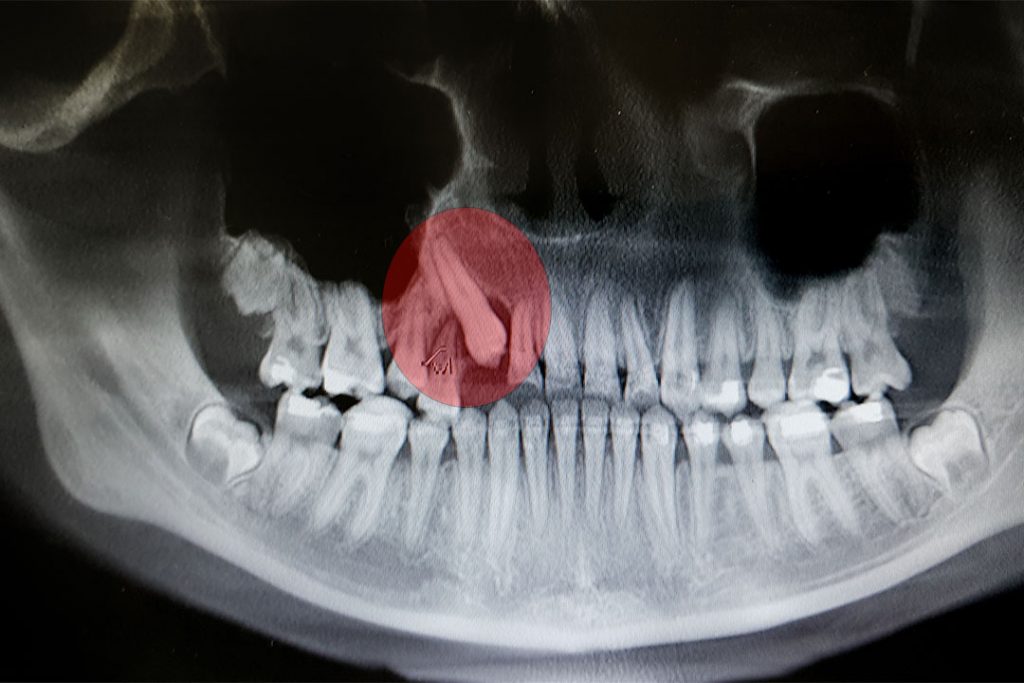

Röntgenbild mit verlangerten Zahn

Um die Position von bewegten Zähnen exakt zu bestimmen, fertigt man in den Oralchirurgischen MVZ-Standorten von Bayerwaldzahn strahlungsarme, zweidimensionale Röntgenaufnahmen (digitales OPG) an. Der Zahnarzt erörtert den ambulanten Eingriff mit Ihnen und legt einen Termin für die operative Zahnosteotomie (Zahnentfernung mit Schnittführung) oder Zahnextraktion (Zahnentfernung ohne Schnittführung) fest, abhängig davon, ob der Zahn schon in den Mund ragt oder nicht. Zur regionalen Betäubung wird eine Injektion gesetzt. Falls mehrere Zähne entfernt werden müssen oder Sie Angstpatient sind, kann eine Vollnarkose angebracht sein In diesem Fall wird der Anästhesist ein Aufklärungsgespräch mit Ihnen führen. Der Entfernungseingriff eines Zahnes dauert ungefähr 20 Minuten. Nach dem Eingriff kann der Patient meist am selben Tag in Begleitung entlassen werden. Vorsorglich wird der Patient außerdem mit Schmerzmitteln versorgt.